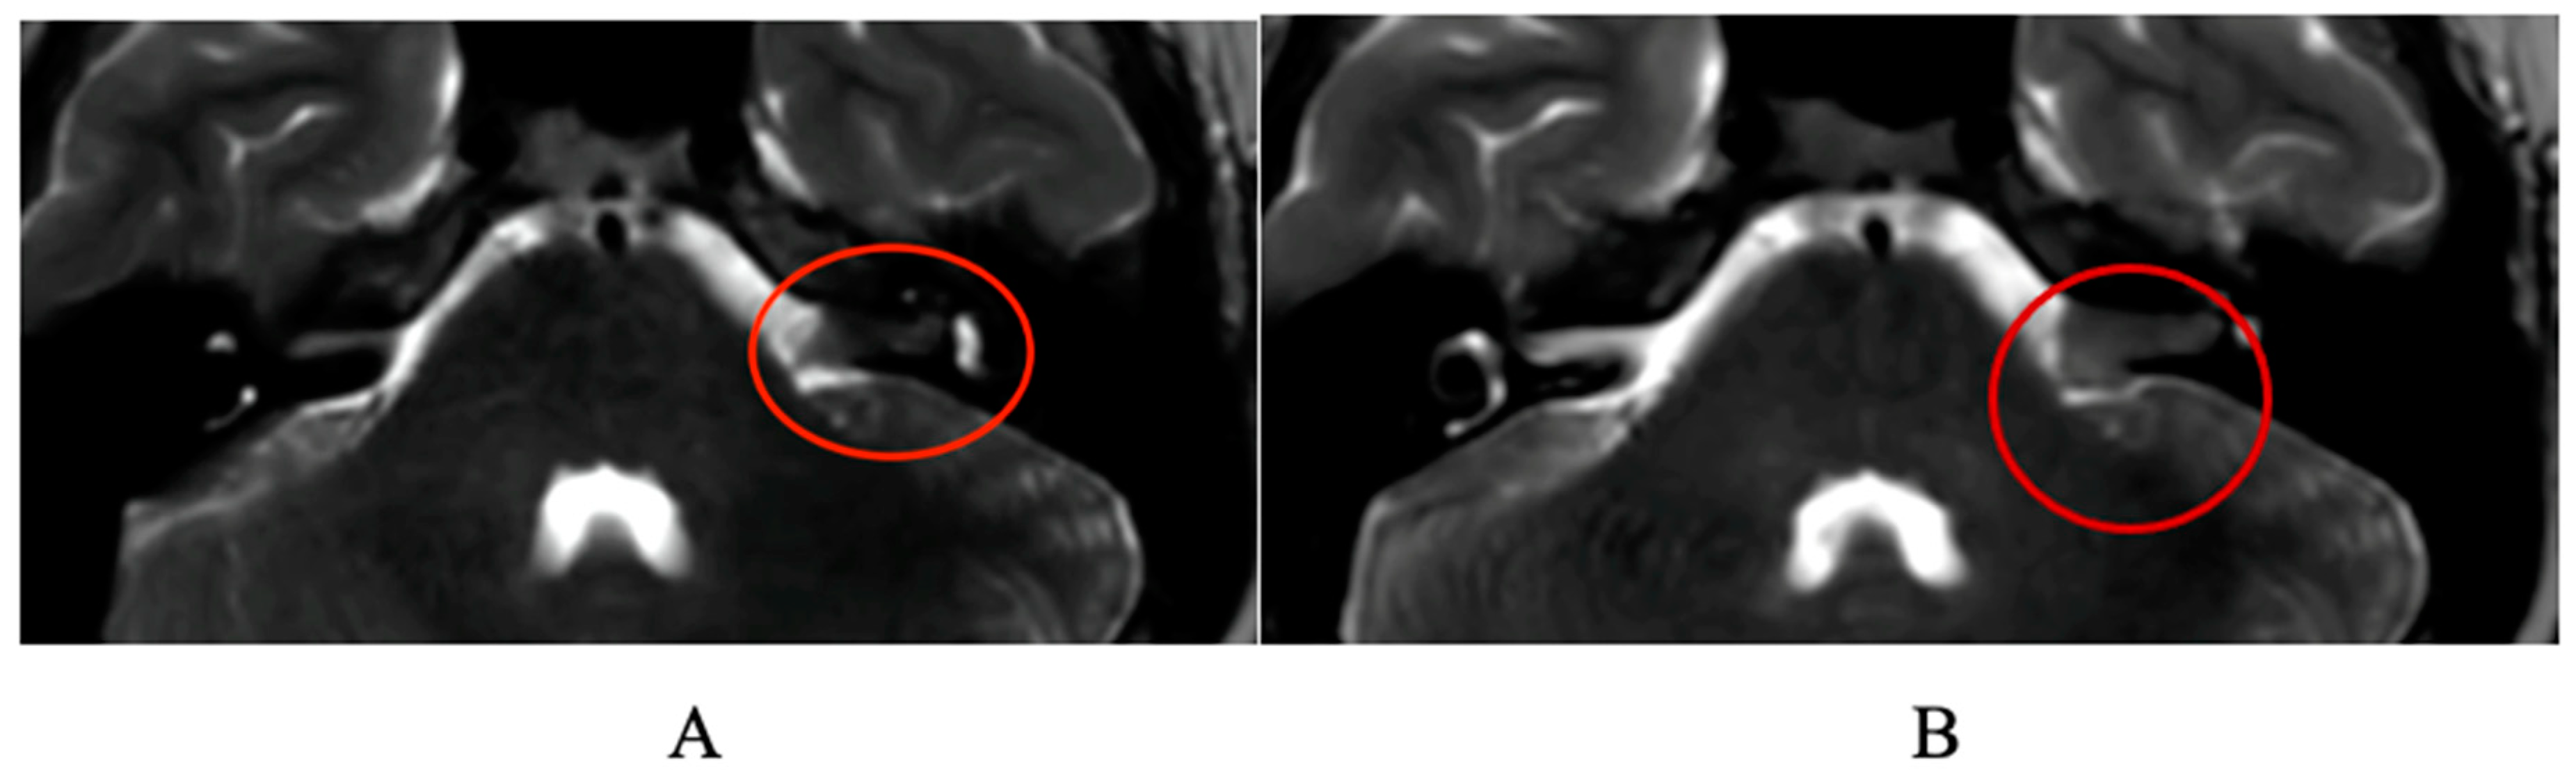

1. Case Report